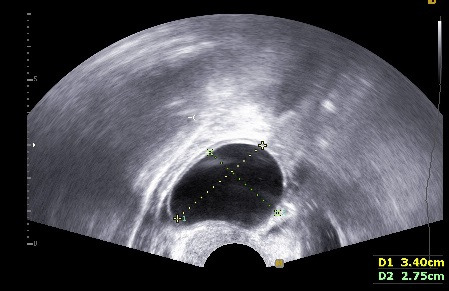

임신을 준비하는 여성들의 초음파 검사에서 관찰되는 영상입니다.

1. 양성종양 (Benign ovarian cyst)

자궁근종이 있는지, 자궁 용종이 있는지, 난소에 혹이 있는지 확인할 수 있는 간편하면서도 정확도가 높은 검사입니다. 비용은 병원마다 천차만별이오니 꼭 미리 확인하고 가시기 바랍니다. 자궁근종, 자궁 용종, 난소에 자궁내막종의 여부에 따라 난임에 대한 접근방법이 바뀔 수 있어 필수적으로 시행하는 검사입니다.